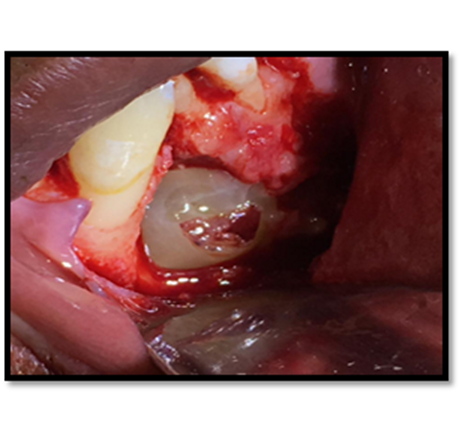

Cirugía propiamente dicha:

Se realizó la osteotomía para el retiro de los dentículos que está formando al odontoma, llegando a la extirpación de 13 dentículos.

Imagen 8. Odontosección.

Imagen 9. Remoción de Odontomas.